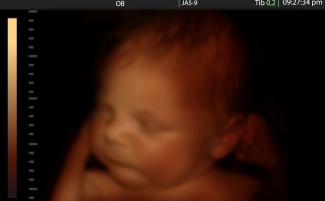

Tvrdila, že je “neuveriteľne zriedkavé”aby dieťa prežilo mimo maternice v 23. týždni, napriek tomu, že v Kanade je to vek životaschopnosti predčasne narodených detí. Okrem toho obrázky predčasne narodených detí v 23. týždni odhaľujú plne sformované dieťa, ktoré môže s lekárskou starostlivosťou prežiť mimo maternice.